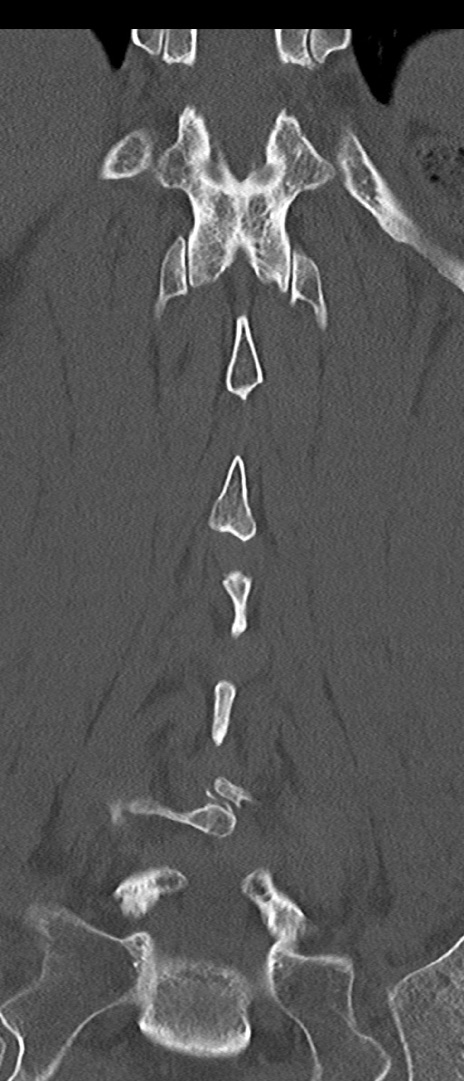

腰椎CT